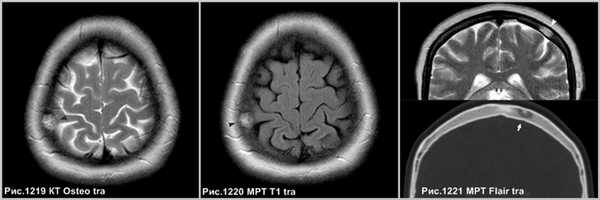

Гемангиома в плоских костях черепа - не частое образование, которое располагается преимущественно в диплоическом слое. Имеется разряженное строение губчатого вещества и толстые костные трабекулы, радиально расходящиеся в стороны. Очаг разряжения губчатого вещества в толще диплоического слоя определяется как зона↓плотности на КТ (стрелка на рис.1221) и↑МР-сигнала на Т2 и Flair (головки стрелок на рис.1219-1221).

Гемангиомы позвонков представляют собой очаговые образования, без масс-эффекта, вызывающие рассасывание большинства вертикальных балок позвонка, однако сохраняющиеся балки склерозируются и утолщаются. В целом вертикальная резистентность позвонка снижается, что может осложняться патологическими переломами. Считается, что гемангиома, содержащая большое количество жира, с меньшей вероятностью, будет расти или станет клинически значимой [87].

![]()

Крупная гемангиома в теле L5 позвонка, распространяющаяся на всё его тело, приводящая к перестройке губчатого вещества кости, с разряжением губчатого вещества и наличием вертикальных утолщенных костных балок (головки стрелок на рис.1222,1223). Гемангиома в теле позвонка, имеющая жировую интенсивность МР-сигнала - ↑сигнал по Т1, с обозначением контура на последовательности в противофазе (головка стрелки на рис.1224), и имеющая выпадение МР-сигнала в режиме Т2 с жироподавлением (стрелка на рис.1224), что соответствует жировой ткани в гемангиоме.